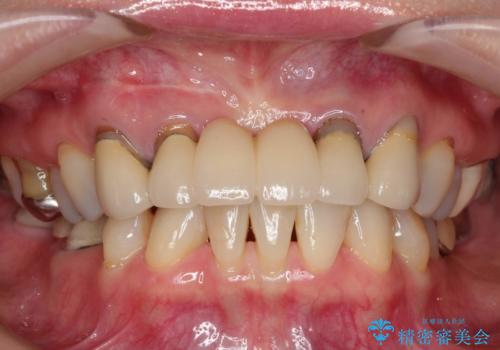

前歯のブリッジの見栄えが悪い→見えないところからしっかりとやり直しを

→根管治療終了後、ファイバーコアを築造し、新しいセラミックブリッジを製作した。

かぶせ物の種類:PFZ standard